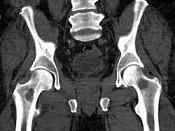

问题 男,46岁,双髋部疼痛,实验室检查血钙升高,尿本周蛋白(+),结合图像,最可能的诊断是?(?)

选项 A.骨髓瘤 B.骨质疏松症 C.骨转移瘤 D.骨囊肿 E.动脉瘤样骨囊肿

答案 A